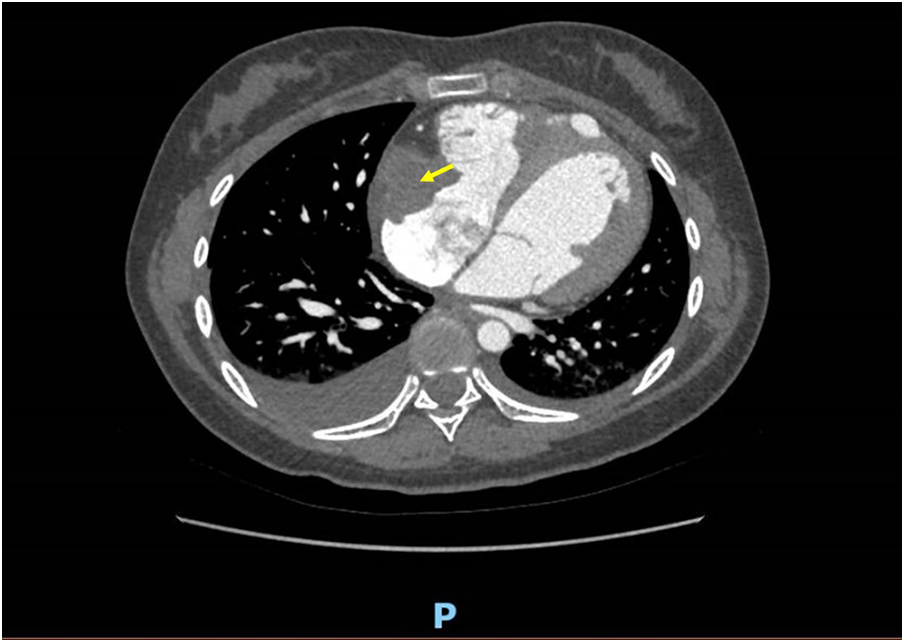

On the fourth day of hospitalization, an enhanced cardiac CT scan revealed a well-defined oblong soft tissue density shadow measuring approximately 30 mm × 34 mm × 32 mm (anteroposterior diameter × transverse diameter × cranio-caudal diameter) within the right atrium and its appendage. The density of the shadow was around 30 Hounsfield units, and no significant enhancement was observed after contrast agent injection, raising suspicion for thrombus formation (Figure 2). Dynamic electrocardiogram reveals sinus bradycardia, an accelerated ventricular escape rhythm, occasional atrial and ventricular premature beats, ST changes, and no significant abnormalities in heart rate variability.

Figure 2

A well-defined, mass-like soft tissue density lesion measuring approximately 30 mm × 34 mm × 32 mm (anteroposterior diameter × transverse diameter × cranio-caudal diameter) is observed at the right atrial appendage and tricuspid valve chordae tendineae. No discernible enhancement is noted on contrast-enhanced imaging.